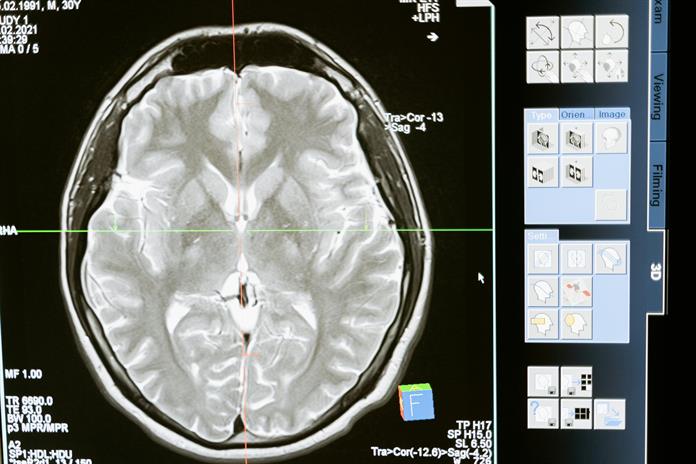

“existe de hecho una enfermedad que es secundaria a sarampión que tenemos mucho sin verla porque nuevamente el pico apenas está empezando otra vez qué es la panencefalitis esclerosante subaguda.

En la literatura está reconocida como una enfermedad crónica del sarampión esta patología se puede presentar hasta diez años después de que dio el sarampión y cuando empiezan los síntomas a veces no pensamos que es por el sarampión, porque el sarampión dio hace diez años, pero tiene varias características que son clásicas”.

Se trata de una enfermedad neurodegenerativa que va afectando de manera progresiva al cerebro y lo va lastimando hasta dejarlo prácticamente destruido.

“se puede presentar al principio con algunas alteraciones cognitivas, algunas alteraciones anímicas, puede avanzar con crisis convulsivas, epilépticas, trastornos del movimiento, trastornos motores hasta llevar al paciente a un estado de coma completamente”.